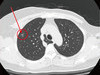

近幾年罹患脂肪肝的人數逐漸提升,其中成因包含肥胖、血脂異常、糖尿病等症狀,以及高油、高糖、不愛運動等生活習慣有關。最近更有醫師進一步指出,脂肪肝跟肉類選擇及烹飪方式也有關係。

肝膽腸胃科醫師錢政弘19日在臉書PO文分享,根據以色列的研究顯示,發現常食用「紅肉」或是「加工肉品」的人,得到脂肪肝的機率會多五成,常食用「燒烤肉品」的人,有多兩倍的機率會有胰島素阻抗(意味著將來糖尿病機率增加)。

過去對於罹患脂肪肝的說法,較常著重在「每日膽固醇」或「總熱量」的控管,然而以色列這項研究結果證實,不論你每天膽固醇或總熱量的攝取量是多少,只要是有吃到「紅肉」或是「加工肉品」就會增加「脂肪肝」的風險,可見肉品種類及食物的處理方式對肝的傷害不小。